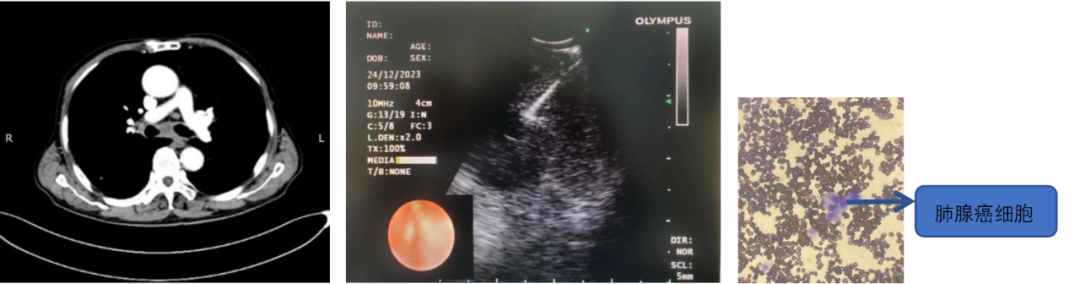

患者,男,70岁,近2个月来“活动后呼吸困难,近日又出现痰中带鲜血”,收住院。胸部增强CT见“左肺下叶外周型占位,肺门、纵膈淋巴结肿大”。张强主任带领团队讨论分析患者病情,高度怀疑为肿瘤性病变,且普通电子支气管镜获取组织困难,病变紧贴主动脉,经皮肺穿刺活检风险大。为明确诊断及分期,决定为患者实施支气管内超声引导下针吸活检术(EBUS-TBNA)+电子支气管镜下病灶活检+现场快速评价(ROSE)。术中ROSE快速诊断查找到肺腺癌细胞,手术过程顺利。最后病理检查明确诊断为肺腺癌,为患者的下一步治疗确定了方向。

支气管内超声引导下针吸活检术,是一种在电子支气管镜前端安装超声探头的设备,结合专用的吸引活检针,可在实时超声引导下对临近气管或支气管的胸内病变进行活检。该技术不仅能实时观察到病灶,同时可帮助确认血管的位置,在提高穿刺诊断阳性率的同时防止误穿血管,减少风险,术中ROSE进一步提高了取材效率,可实现精准、高效、安全的明确诊断,又可大大减少对患者的损伤。